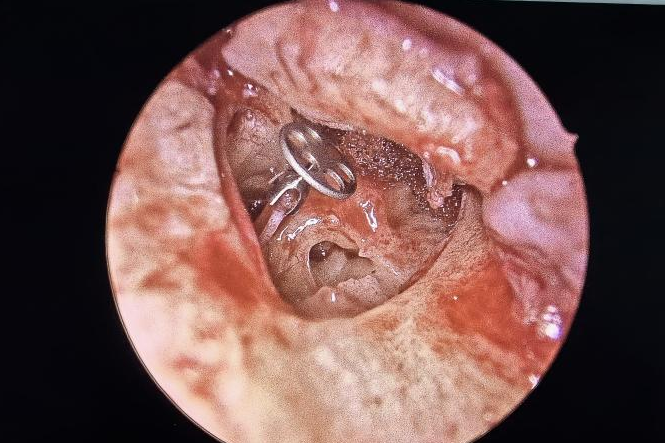

耳朵反复流脓、听力下降还有异味?当心,这可能是慢性化脓性中耳炎的症状。由于早期症状时好时坏,很多人觉得不是大问题,但拖延不治可能对听力造成不可逆的损伤。今天我们就来认清它的真面目,学会如何科学应对。 什么是“慢性化脓性中耳炎”? 慢性化脓性中耳炎,俗称“灌耳心”,典型症状包括耳内反复流脓(常为脓性分泌物,严重时可伴有臭味)、听力下降以及耳鸣等,部分患者还可能伴有眩晕。很多人是从小时候就开始出现症状,尤其是耳朵进水后容易急性发作或加重,成年后,听力持续减退往往成为主要困扰。 如果不及时治疗,炎症可能“向上”蔓延到颅内,引发脑膜炎、脑脓肿等危及生命的严重并发症。也可能侵犯面部神经或平衡器官,导致面瘫、持续眩晕或平衡障碍。最直接的后果是听力会不可逆地下降,严重时可能导致完全失聪。 “慢性化脓性中耳炎” 如何治疗? 慢性化脓性中耳炎的基础治疗需先用双氧水或生理盐水清洗耳道脓液,再滴入敏感抗生素耳液(如氧氟沙星滴耳液)。急性发作或重症时需口服或静脉注射抗生素并辅以抗炎药。若药物控制不佳或已有器质性病变,则需手术,包括乳突切除术清除病变组、鼓膜成形术修复穿孔鼓膜、听骨链重建术改善传音功能及胆脂瘤清除术清除胆脂等。 患者常见问题解答 问 手术后多久能恢复听力? 答 术后恢复情况与手术方式、个人身体情况有关。若为鼓膜修补手术,术后1—3个月左右,听力会逐渐改善,若进行听骨链重建手术,通常需要 3 到 6 个月,听力才能趋于稳定。术后需定期复查,监测听力恢复情况。 问 儿童患者能手术吗? 答 如果孩子的病情确实需要手术,家长不用太担心,儿童也是可以接受手术治疗的。医生会根据孩子的年龄大小、病情严重程度,选择最适合的手术方式,比如现在常用的微创技术,就能尽量减少手术对孩子耳朵的创伤,让孩子恢复的更好。 问 如何预防复发? 答 术后严格遵医嘱用药、复查,避免感冒及耳部进水,保持鼻腔通畅,减少咽鼓管阻塞。 贵州航天医院耳鼻咽喉科简介 张光进 中共党员,耳鼻咽喉科主任,副主任医师 临床擅长:对耳鼻喉头颈常见病的诊治具有丰富的临床经验,擅长鼻内镜、耳内镜、耳显微、头颈咽喉部肿瘤及眩晕手法复位等的诊疗。 曾先后前往第三军医大学西南医院、复旦大学耳鼻喉科医院、上海新华医院及北京友谊医院进修学习;遵义市医学会常务委员;主持及参与级科研课题2项,发表专业论文10余篇。 陈维信 九三学社社员,耳鼻咽喉科主任医师 临床擅长:对耳鼻咽喉科常见疾病的诊治具有丰富的临床经验,擅长耳、鼻、喉及头颈部位的手术。 曾先后前往上海交通大学附属仁济医院耳鼻喉-头颈外科、北京大学人民医院耳鼻喉-头颈外科参加鼻内镜外科进修学习。中国睡眠研究会委员,贵州省医学会耳鼻喉-头颈外科学分会委员,贵州省耳鼻喉-头颈外科学会理事,贵州省医学会变态反应学分会委员,贵州省防聋治聋技术指导组专家,遵义市耳鼻喉科分会副主任委员,遵义市医疗事故鉴定专家库成员;主持省部级科研课题2项,发表专业论文20余篇。 秦 晋 耳鼻咽喉科副主任医师 临床擅长:对耳鼻咽喉科常见疾病的诊治具有丰富的临床经验,擅长耳、鼻、喉及头颈部位的手术。 遵义市医学会常务委员;曾先后在第三军医大学西南医院、湖南湘雅鼻颅底培训班进修学习。 贵州航天医院耳鼻咽喉科简介 基本情况 贵州航天医院耳鼻咽喉科拥有一支经验丰富、技术精湛的医疗团队,共有医师9名,其中副高级以上专家5名,医学硕士2名,开放床位20张,拥有德国WOLF鼻窦内窥镜系统、日本奥林巴斯电子喉镜、奥林巴斯电子鼻咽镜、丹麦临床听力监测设备、声导抗仪、听觉诱发电位、耳声发射仪、美国杰西低温等离子治疗仪、杭州好克鼻窦内窥镜系统、鼻动力系统、耳显微镜、耳用电钻、微波治疗仪等设备。 专科特色 (一)耳部疾病 耳内镜下胆脂瘤切除术、III型鼓室成形术+人工听骨链重建术。 (二)鼻部疾病 内镜下鼻息肉切除术、鼻窦功能开放术。 (三)咽喉疾病 内镜下扁桃体、腺样体低温等离子切除术 (四)交叉学科 1.经鼻内镜下眶内肿瘤切除术 2.经鼻内镜下鼻腔泪囊吻合术 诊疗范围 (一)常见耳疾的诊断和治疗:中耳炎、耳聋、耳鸣等。通过各种耳科检查手段,如耳镜检查、听力测试和耳脑干听觉诱发电位检查等,准确诊断患者病情,制定个性化治疗方案。 (二)鼻炎、鼻窦炎、鼻出血等鼻科疾病的诊断和治疗:采用微创技术,如鼻内窥镜检查、低温等离子手术等,为患者提供有效的治疗方案。 (三)喉炎、声带息肉、声带白斑等喉科疾病的诊断和治疗:通过声带电子镜、喉镜等设备,准确判断患者的喉部病变,为患者提供精准的治疗方案。 (四)鼻眼、鼻颅底相关手术。